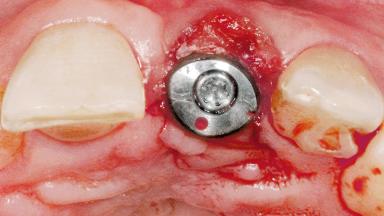

Late Flapless Placement of an Implant in a Maxillary Left Central Incisor Site

Type of Implants One-Piece

Attachment One-Piece

Defining Characteristics One missing tooth to be replaced by an implant-borne prosthesis

Placement Protocol Early or late implant placement